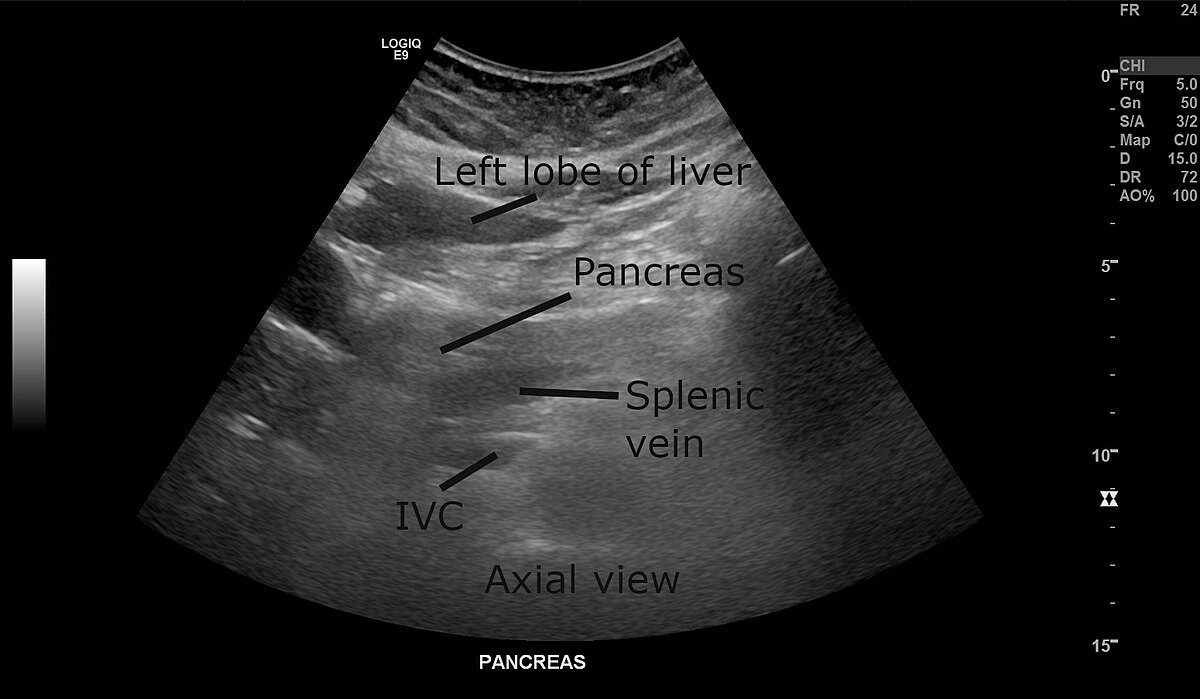

Alright, let’s get cozy with some digestive science for a second. Your abdomen is basically a winding maze for food. Along the way, air sneaks in—or gets created as stuff ferments. That’s bowel gas. The pancreas (kind of a shy, important organ behind your stomach) sometimes gets hidden on ultrasound, not because it’s gone, but because… well… your gas is just in the wrong place at the wrong time!

This is called overlying bowel gas, and it’s super common. According to several doctors I’ve chatted with (and a quick scroll through med forums), almost everyone gets some scanned images messed up by gas now and then. It’s just that, for some folks, it happens every single time—especially if you’re already feeling bloated, have IBS, or you just scarfed down a carbonated beverage before your appointment. Want more details on this? Head over to Why is my pancreas obscured by bowel gas for a deeper dive.